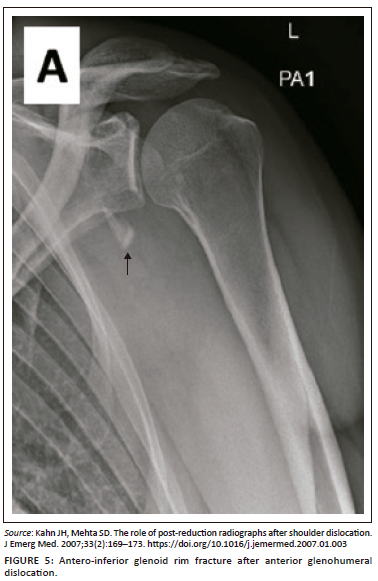

Control plain radiographs are mandatory. Three views must be obtained (anteroposterior, axillary view and lateral view) to confirm the reduction and rule out bony compression fractures of the humeral head (Hill-Sachs lesion), push-off fractures of the glenoid (bony Bankart lesion), bony erosions (glenoid bone loss) or to identify fractures that were initially not visible (Figure 2, Figure 3, Figure 4 and Figure 5). Kahn and Mehta reported a rate of 37.5% of fractures which were visible only on post-reduction radiographs.15